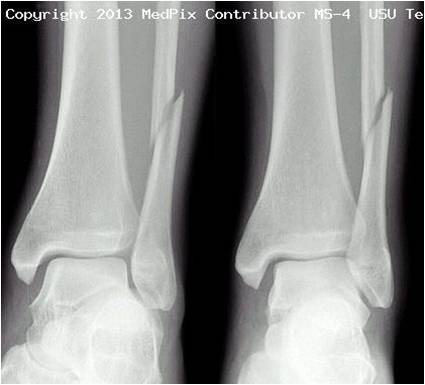

Diagnosis

- 3 views:

- AP

- Best for isolated lateral and medial malleolar fractures

- Oblique (mortise)

- Best for evaluating for unstable fracture or soft tissue injury

- At a point 1cm proximal to tibial plafond space between tib/fib should be ≤6cm

- Lateral

- Best for posterior malleolar fractures

X-rays

- Tintinalli, Uptodate, Radiopaedia.org (Images by Dr. Frank Gaillard), Medpix Radiology Teaching Files (Images by Dr. Timothy Sanders)